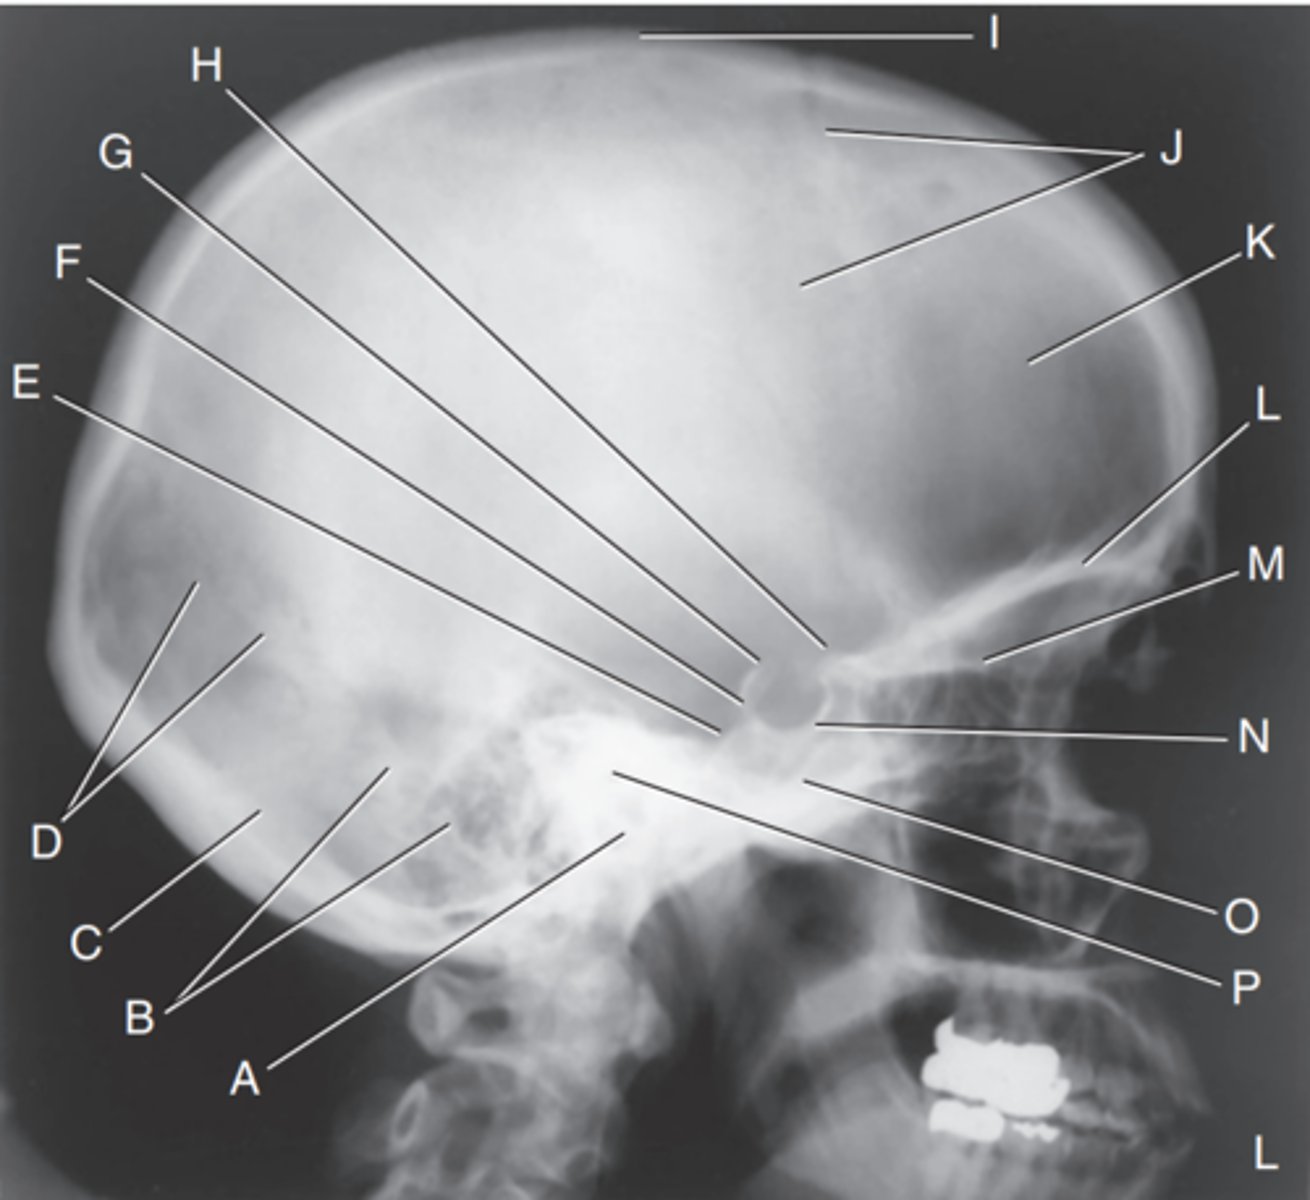

EAM

Label A

Mastoid portion of temporal bone

Label B

Occipital bone

Label C

Lambdoidal suture

Label D

Clivus

Label E

Dorsum sellae

Label F

Posterior clinoid processes

Label G

Anterior clinoid processes

Label H

Vertex of cranium

Label I

Coronal suture

Label J

Frontal bone

Label K

Orbital plates

label L

Cribriform plate

Label M

Sella turcica

Label N

Body of sphenoid (sphenoid sinus)

Label O

Petrous portion of temporal bone

Label P